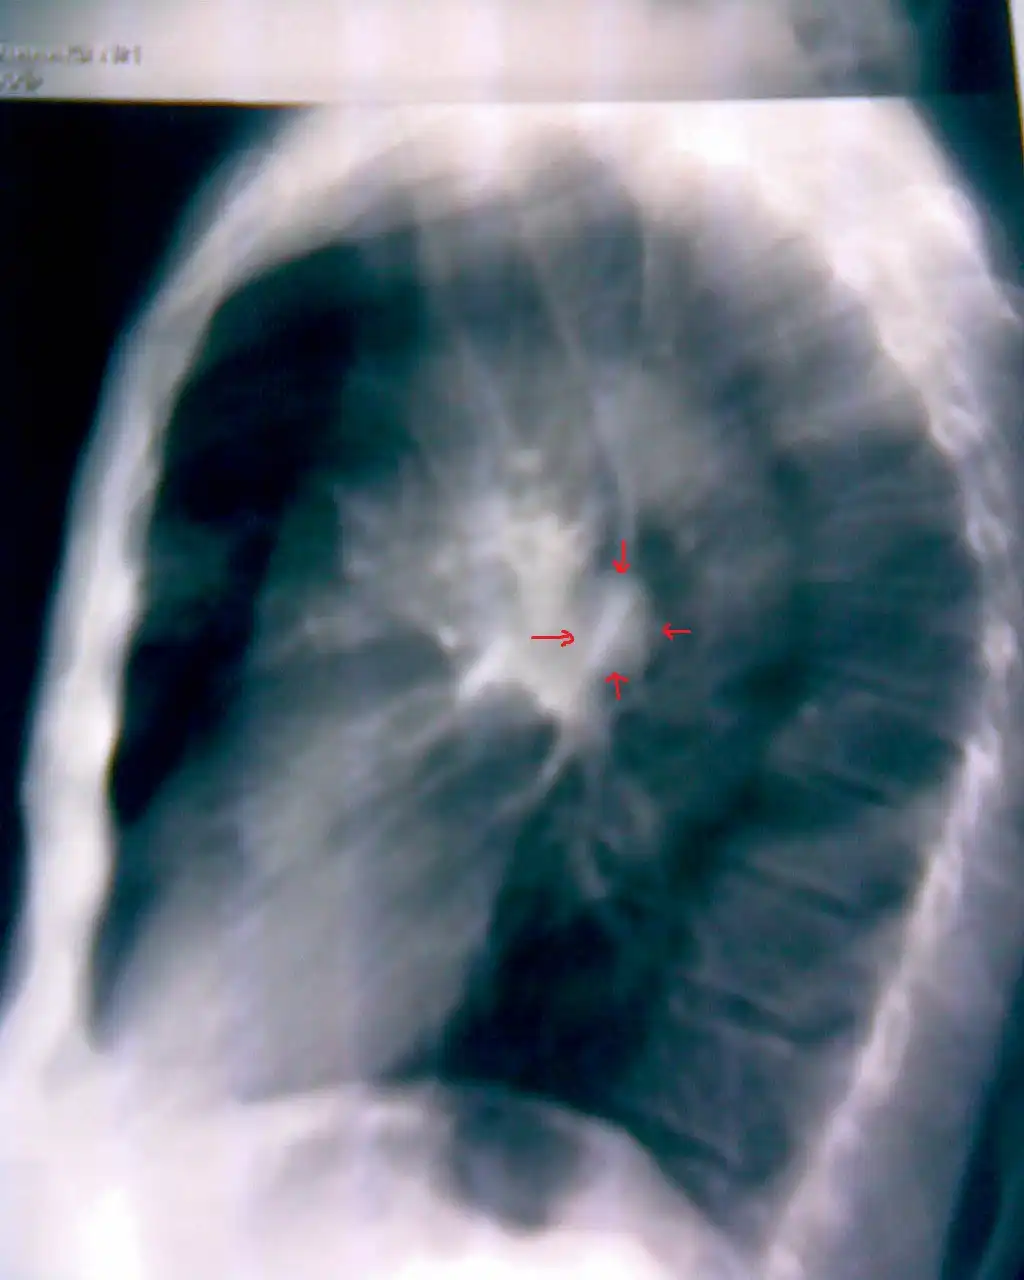

Линейная томограмма:

2. По поводу снимков... Сомнение вызывает первый пациент. 2 фокуса в разных легких... Разве что метастазы в прикорневые л\у правого легкого... Да и контуры очень четкие в левом легком... Верхняя доля... Дорожка к корню... Больше похоже на туберкулез ИМХО. Хотя и лучистость есть... Спорно.